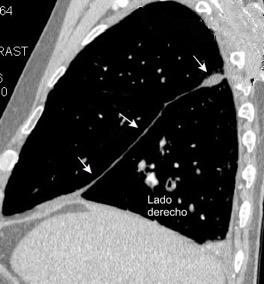

Marzo 2014: Perforación longitudinal distal secundaria a episodio de vómito (síndrome de Boerhaave). Derrame pleural izdo. que evoluciona a empiema.

Wang C-T et al. Tension hydropneumothorax in a Boerhaave syndrome patient: A case report . World J Emerg Med, 2021. Katabathina V et al. Nonvascular, nontraumatic mediastinal emergencies in adults:a comprehensive review of imaging findings. Radiographics. 2011.